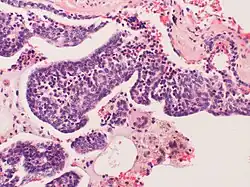

Pulmonary neuroendocrine cells (PNECs) are specialized airway epithelial cells that occur as solitary cells or as clusters called neuroepithelial bodies (NEBs) in the lung. Pulmonary neuroendocrine cells are also known as bronchial Kulchitsky cells.[2] They are located in the respiratory epithelium of the upper and lower respiratory tract. PNECs and NEBs exist from fetal and neonatal stages in the lung airways.

These cells are bottle- or flask-like in shape, and reach from the basement membrane to the lumen. They can be distinguished by their profile of bioactive amines and peptides, namely serotonin, calcitonin, calcitonin gene-related peptide (CGRP), chromogranin A, gastrin-releasing peptide (GRP), and cholecystokinin.

These cells can be the source of several types of lung cancer, most notably small cell carcinoma of the lung, and bronchial carcinoid tumor.[3][4]